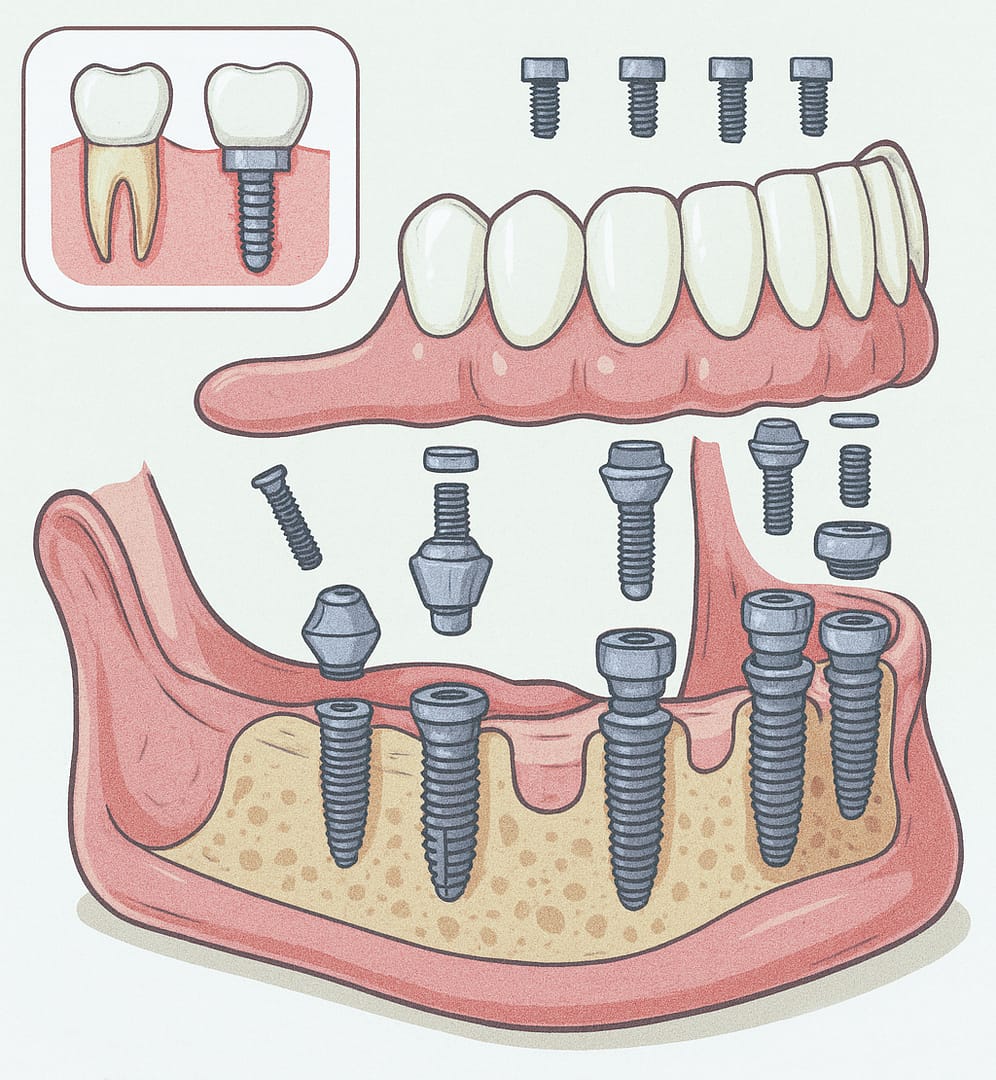

Prótesis total sobre implante

Reemplaza todos los dientes ausentes de una arcada completa. Se fija de forma atornillada sobre los implantes, brindando una solución fija, estética y funcional para pacientes con pérdida dental total.